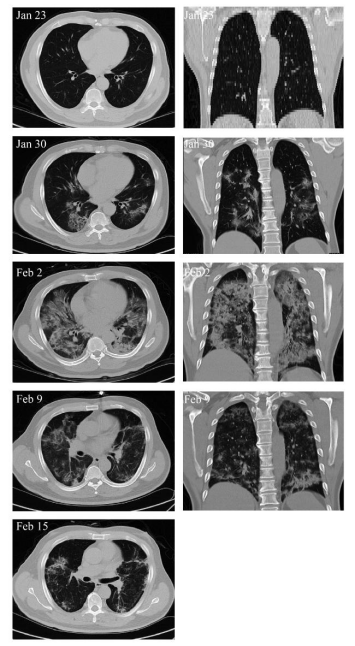

從該患者的胸部CT圖像可以看到,患者最初未見(jiàn)肺炎表現,后來(lái)雙側多葉發(fā)生毛玻璃樣混濁和肺炎浸潤,很快肺炎侵襲整個(gè)肺部。在細胞移植9天后,肺炎滲透大體消退。痊愈后,肺部只留下少量的磨玻璃不透明結節。

▲患者1的胸部CT圖像